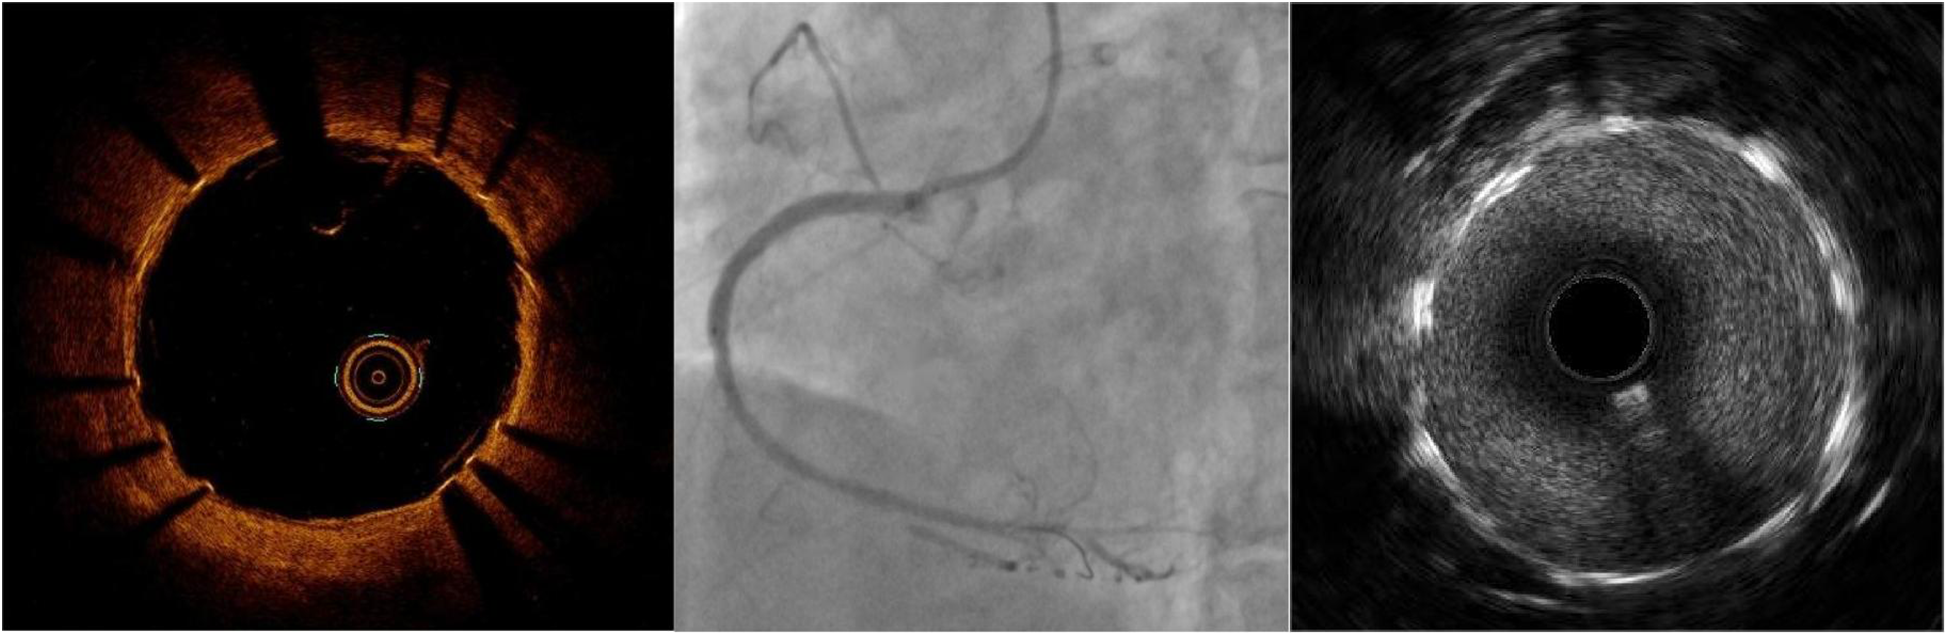

Physical examination revealed no significant abnormalities. Laboratory test results (Table 1) indicated poor glycemic control, dyslipidemia, and mild liver dysfunction. The initial ECG (Figure 1) showed R-wave progression in anterior leads and the presence of pathological q waves in lead III and aVF. Cardiac ultrasound revealed the following measurements: left ventricular diameter 48.5 mm, interventricular septal thickness 10.4 mm, left ventricular posterior wall thickness 10.2 mm. The echocardiogram revealed regional wall motion abnormalities with a preserved global left ventricular ejection fraction of 61.5%. Despite optimized pharmacotherapy, recurrent angina symptoms persisted over the preceding 2 weeks, which were not resolved. Therefore, a coronary angiography was performed (Figures 2a–d), which revealed normal stent conditions in the left anterior descending artery and circumflex artery, while an aneurysmal bulge was observed in the right mid-coronary artery with proximal and distal restenosis. We conducted intravascular ultrasound (IVUS) of the right coronary artery (Figures 2e,f), identifying new atherosclerotic plaques as the cause of restenosis. The proximal lumen bulge area exhibited incomplete vascular wall structure, leading to a diagnosis of pseudoaneurysm. Coronary angiography revealed that the maximum diameter of the pseudoaneurysm was approximately 8.70 mm (Figure 3b).

Figure 2

Coronary angiography and intravascular ultrasound. (a) Normal imaging of the LAD stent; (b) normal imaging of the LCX stent; (c) imaging of in-stent restenosis and coronary artery aneurysm in the RCA; (d) imaging of post-balloon dilation in the RCA; (e) IVUS image of newly formed atherosclerotic plaque; (f) IVUS image of coronary artery aneurysm, lacking the normal three-layer structure of arteries.

The yellow triangle shows coronary artery aneurysm.

The red arrow shows newly formed atherosclerotic plaque.